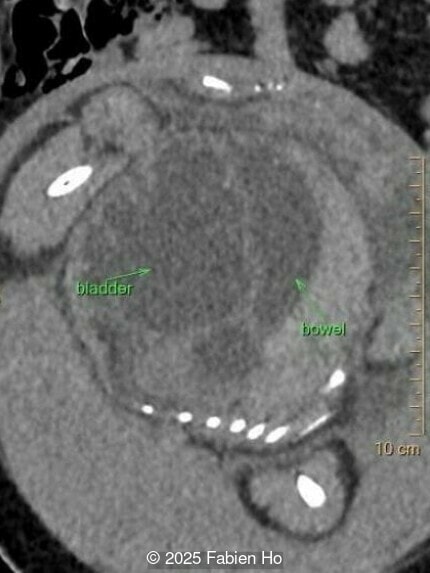

Axial image of the abdomen

Image 7 Axial image of the abdomen

Axial image of the fetal pelvis

Image 14 Axial image of the fetal pelvis

Our prenatal ultrasound revealed a male fetus with megabladder, dilation of both ureter and kidneys, and thinned kidney parenchyma consistent with Lower Urinary Tract Obstruction (LUTO).  Additional findings suspected on ultrasound and confirmed on computed tomography included:

• Suspicion of dilated bowel in the left flank, in addition to dilated urinary tract